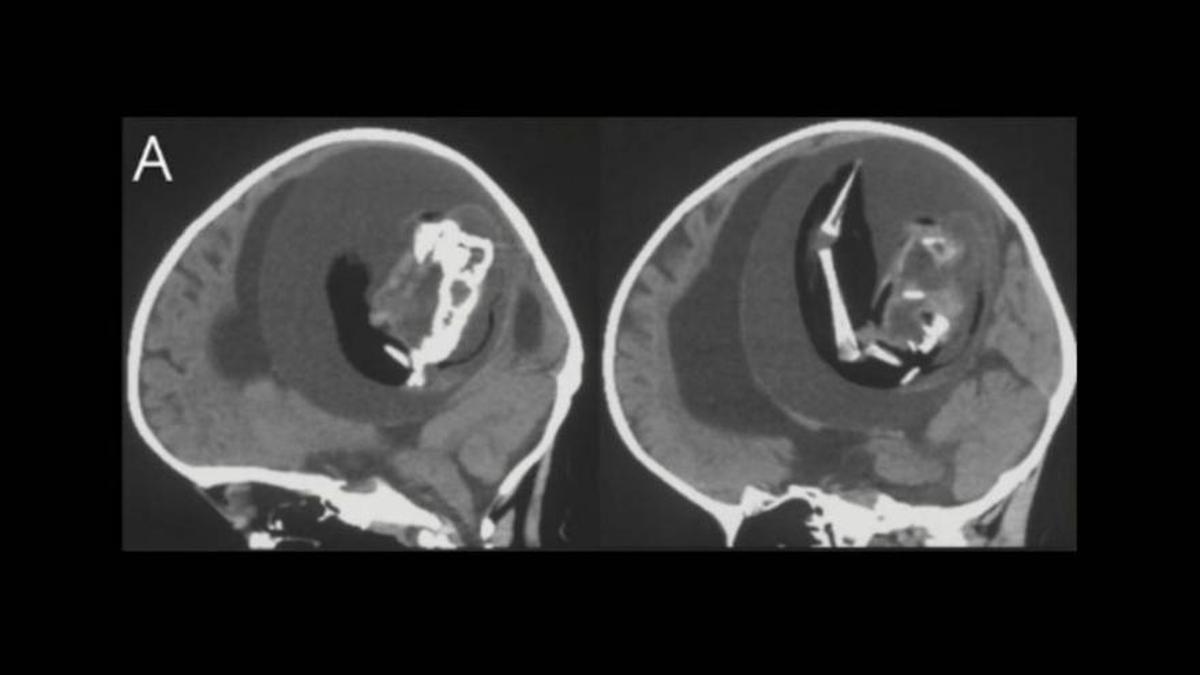

A les imatges cerebrals de la nena d'1 any, els científics van poder observar el fetus amb una columna vertebral i altres estructures òssies / ZONGZE LI ET AL / NEUROLOGY

En aquest cas, com es pot veure en una publicació a Twitter de l'especialista Oren Gottfried de la Universitat de Duke, als Estats Units, que no va participar de l'estudi, el fetus del “bessó paràsit” mostrava indicis clars de desenvolupament. Els estudis van revelar que el fetus disposava d'una columna vertebral i dos ossos de la cama, concretament el fèmur i la tíbia, juntament amb “brots” en forma d'extremitats superiors i dits.

A més, patia d'espina bífida, una afecció on part de la medul·la espinal queda exposada, en lloc d'estar coberta per teixits de l'esquena. Tot indica que el fetus es va allotjar al cervell durant un procés de desenvolupament anomenat plegament de la placa neural, un pas imprescindible per a la formació de l'estructura del cervell i la medul·la espinal. Només s'han documentat científicament uns 200 casos de fetus en fetus, dels quals únicament 18 van tenir lloc dins del crani.

Segons un article publicat al Miami Herald, el fetus extret tenia uns 10 centímetres de llarg. Les proves d'ADN van confirmar que es tractava del bessó de la nena, que havia continuat creixent a l'interior de la seva germana, ajudat pel subministrament regular de sang. El 1982, un estudi va informar d'un cas similar, en què es va haver d'extreure un fetus de 14 centímetres de llarg, amb extremitats, un tors, un cap i altres característiques reconeixibles, del crani d'un nen de 6 setmanes de vida.